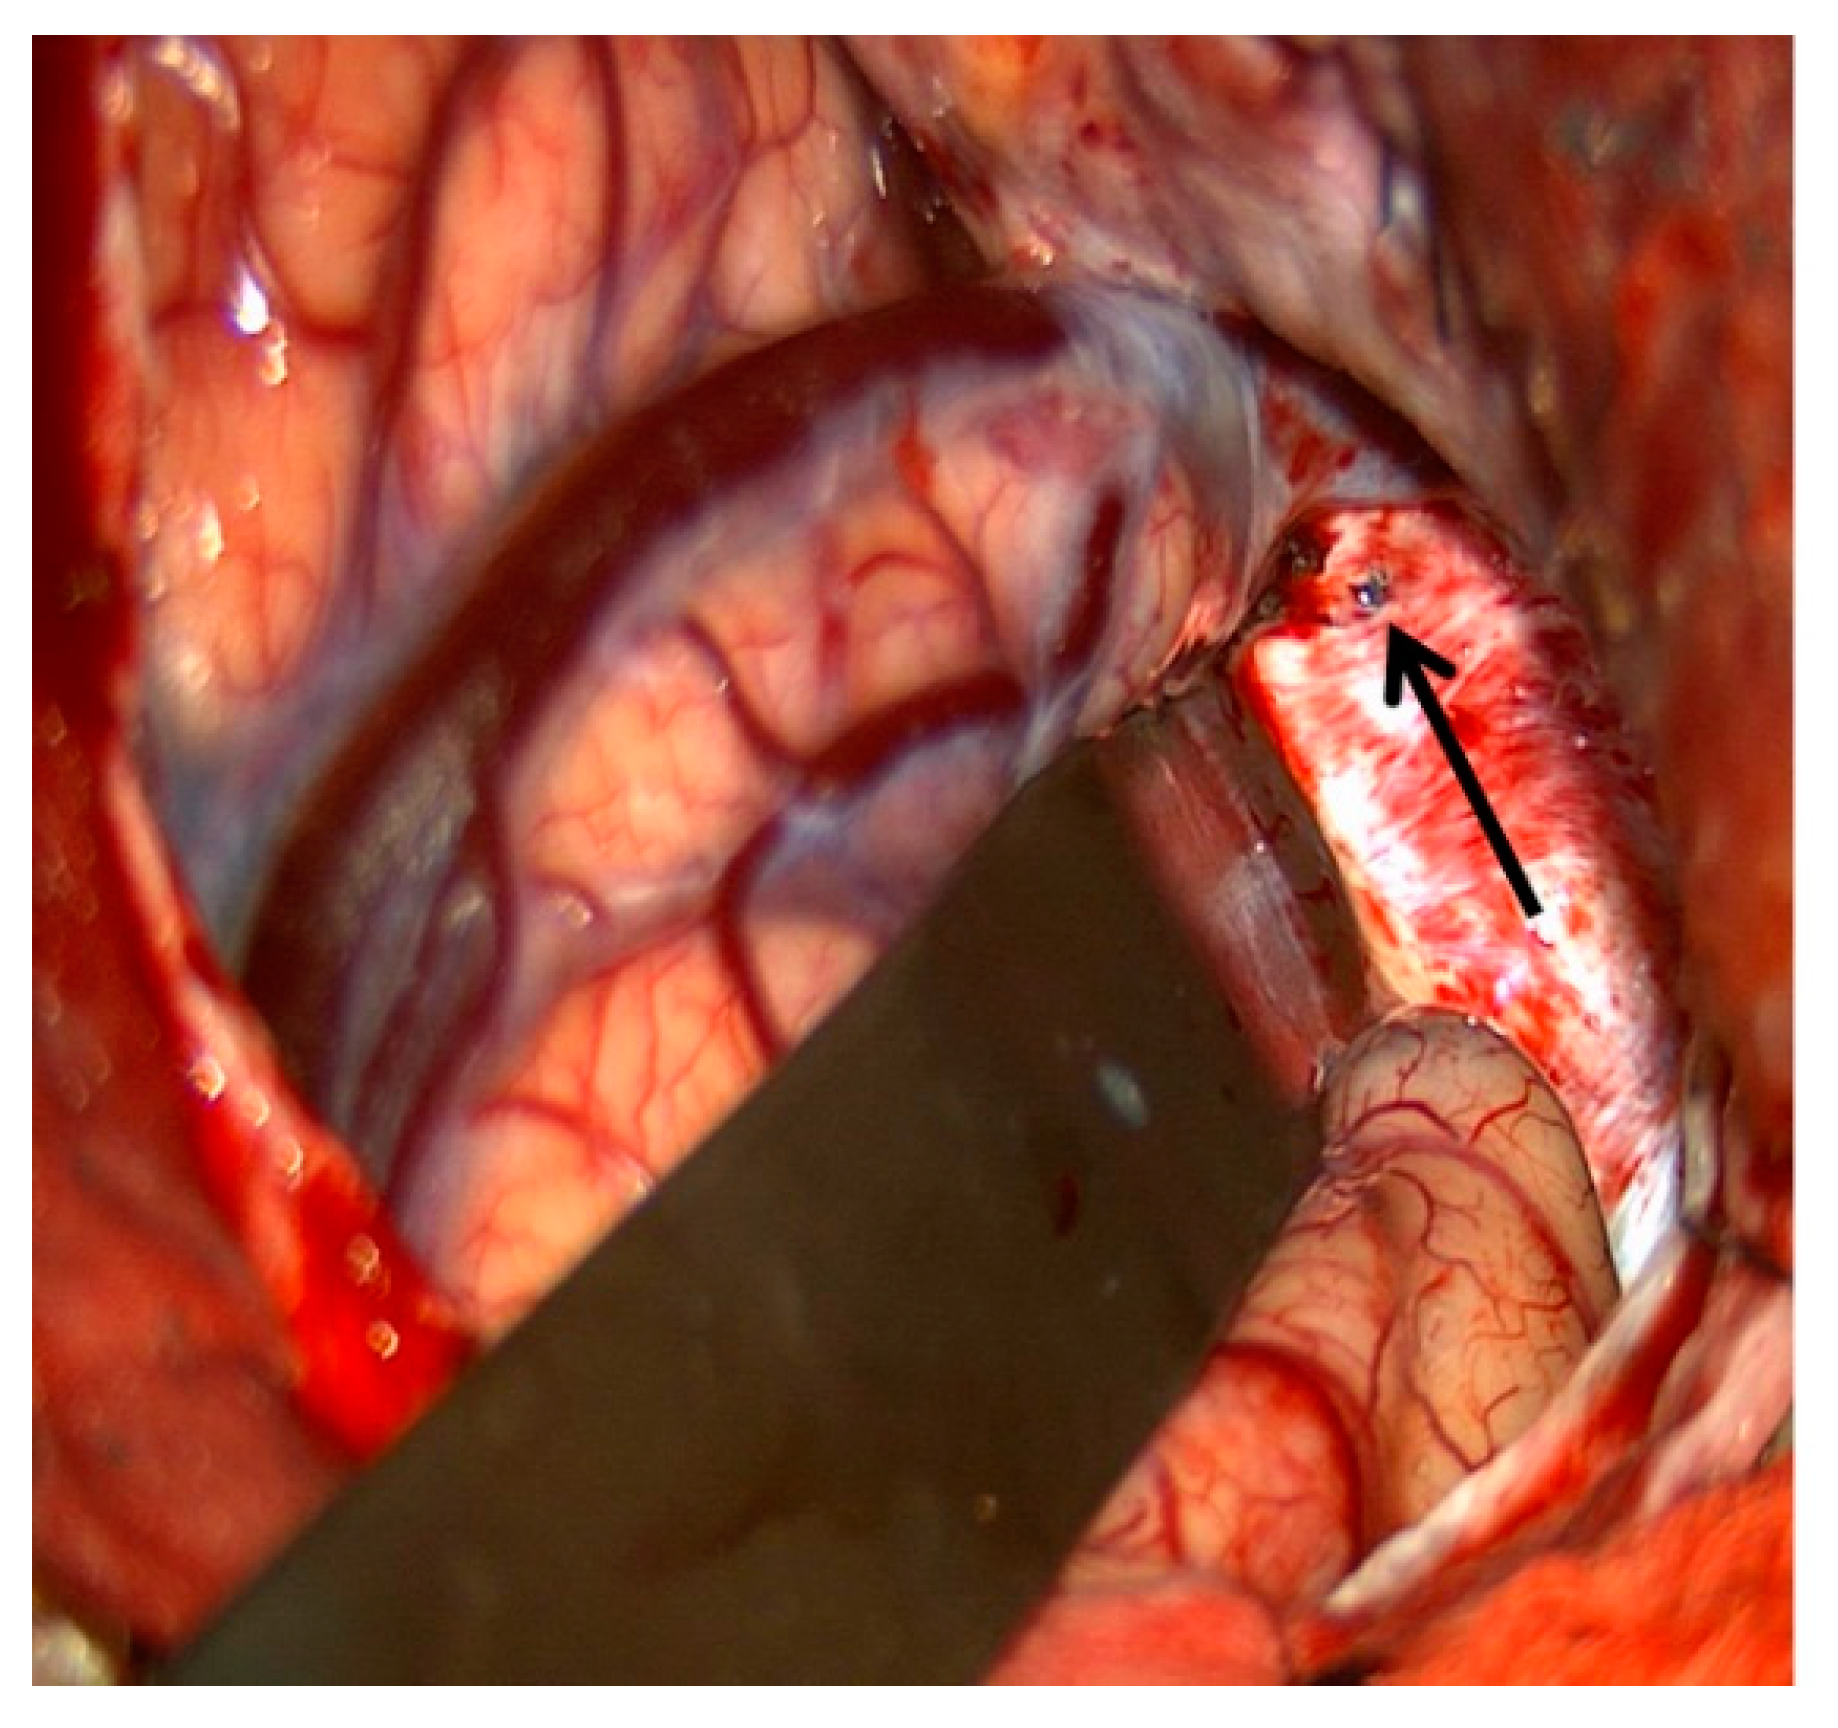

Figure 9. Demonstrates surgical exposure of the lateral wall of the right cavernous sinus via a pre-temporal approach (left). The arrow shows the site of spinal needle puncture in the lateral wall of the cavernous sinus.

11. Surgical Exposure of the Cavernous Sinus

Despite the multiple routes to the CS available to the endovascular surgeon, in some cases, the venous anatomy and location of the fistula site make treatment with endovascular techniques alone inadequate. In these cases, open microsurgical exposure of the CS combined with endovascular embolization may be an option. Staged microsurgical obliteration of residual DAVFs after incomplete endovascular embolization is well published [4,25,26]. However, simultaneous open surgery and endovascular embolization of CCFs are less commonly reported. Krisht et al. reported the treatment of a dural CCF in which the lateral wall of the CS was surgically exposed and dissected prior to cannulation and coil embolization [27]. Geurrero et al. reported a similar case in which a pretemporal, extradural approach to the lateral CS was utilized for treatment of a dural CCF. Once the lateral wall was exposed, the CS was cannulated under ultrasound guidance prior to embolization of the fistula with coils [28]. We have reported the treatment of a paracavernous venous plexus fistula with an open surgical approach combined with endovascular embolization [29]. Through a pterional craniotomy, an intradural pretemporal approach to the lateral wall of the cavernous sinus was performed. Using a preoperative CT angiogram and intraoperative neuronavigation, the exact location of the fistula site within the paracavernous venous plexus was identified. Next, the tip of a spinal needle, registered to and guided by neuronavigation, was introduced into the fistula. An angiogram through the spinal needle was then performed to confirm positioning within the fistula sac without filling of the ICA (Figure 9). After injection of Onyx embolic material into the fistula, intraoperative transfemoral angiogram confirmed complete obliteration of the fistula. Secondary to the risks involved with open surgery, this type of combined approach is generally reserved for fistulas that have failed embolization by traditional endovascular routes. However, as in the above report, DAVFs with fistula sites in paracavernous locations can make treatment by traditional transvenous routes technically impossible. It is in these cases that combined open surgical and endovascular embolization can be useful.